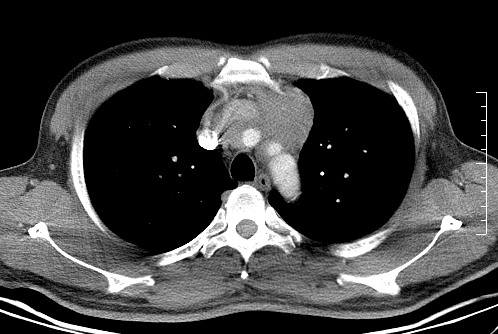

男   40   反复腹痛入院行彩超检查示胸骨右缘4、5肋间不均质回声团

淋巴瘤:前纵隔可见多组肿大的淋巴结,部分融合,有液化坏死

上区却那么有点象占位,胸腺瘤不太象,一点强化也没有,淋巴瘤气管前上腔静后却很干净,下区也点象纵隔积血征,

莲蓬籽征  考虑淋巴瘤